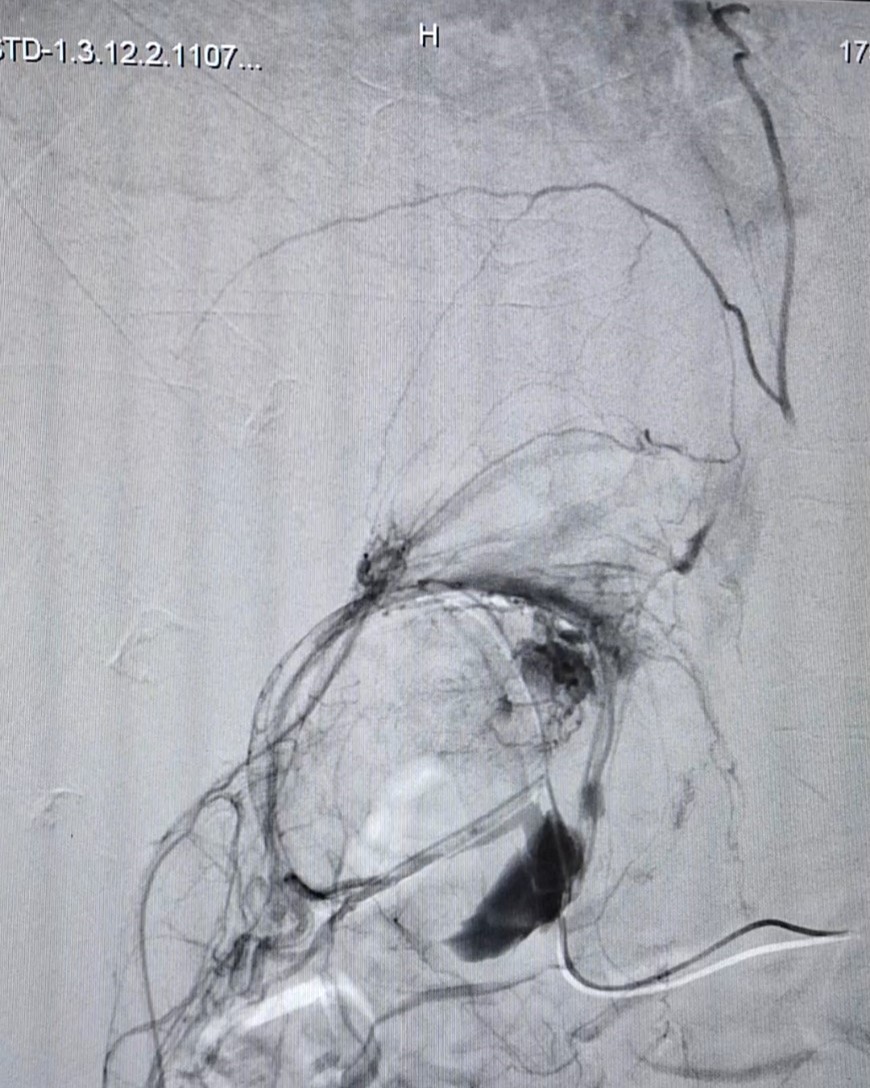

Bệnh viện Quân y 175: Điều trị thành công cho bệnh nhân bị u cơ mỡ mạch thận có xuất huyết trong u

02/11/2023 10:43

(ĐCSVN) - Bệnh nhân được điều trị bằng phương pháp can thiệp nội mạch dưới hướng dẫn của hệ thống chụp mạch máu xóa nền (DSA). Sau 30 phút thực hiện thủ thuật, tình trạng bệnh nhân ổn định, xuất viện sau 1 ngày và hẹn tái khám sau 3 tháng.